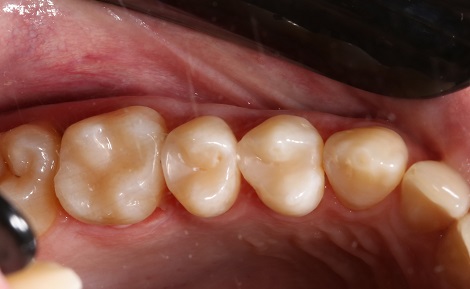

Пломбування кореневих каналів.

Якісно запломбовані кореневі канали є основою

довговічності. Тому очищення і пломбування кореневих каналів в «Домі Стоматології»

приділяється особлива увага! Після пломбування кореневих каналів проводиться

контроль якості пломбування за допомогою знімка.